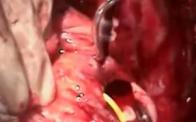

Mitral Valve Replacement: How to Handle the Big MAC

A short presentation on some of the techniques used to address MAC (mitral annular calcification) is followed by an operative video demonstrating several of the techniques. Techniques discussed include mechanical debridement, CUSA debridement, supra-annular MVR, and infra-annular MVR.